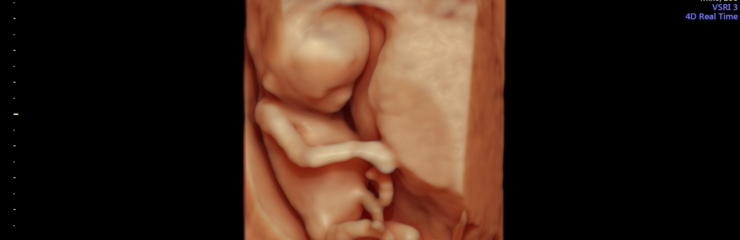

Loode:

Loode kaalub umbes 450 grammi ja liigub aktiivselt. Tal on juba kulmud ja ripsmed. Loode on tõenäoliselt kõige aktiivsem siis, kui naine puhkab. Kasvavad esimesed tõelised juuksed.

Kaelalülid on selgelt nähtavad. 23. nädalal kaalub loode umbes 550 grammi. 23. nädalast on hea visualiseerida 4D ultraheliuuringu käigus loote näojooni.

24. nädalal on loode umbes 30 sentimeetri pikkune ja kaalub umbes 650 grammi.

Uuringud/tegevused:

- Emakapõhja kõrguse mõõtmine

- Loote südamelöökide kuulamine

- Soovi korral 4D ultraheliuuring (24.–32. nädal)